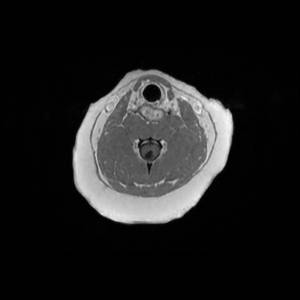

Main Gallery

Playing with a photo gallery function. It is possible to have multiple galleries, each within a namespace.